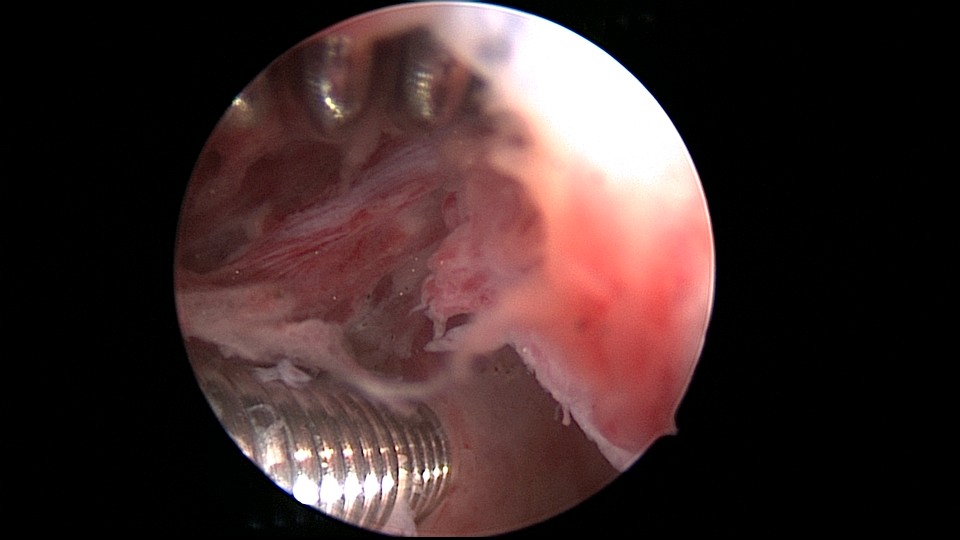

患者49岁,G1P1,顺产1次。安环13年,月经紊乱1月,外院取环失败。B超提示O型环嵌顿,宫腔镜见宫颈管及宫腔组织充血,宫腔广泛粘连,节育环嵌顿、扭曲,异物钳配合中弯钳拉出节育环,环变形、断裂,宫壁节育环嵌顿处见割裂痕迹,无出血,检查宫腔各部,无节育环残留。

图片发自160App